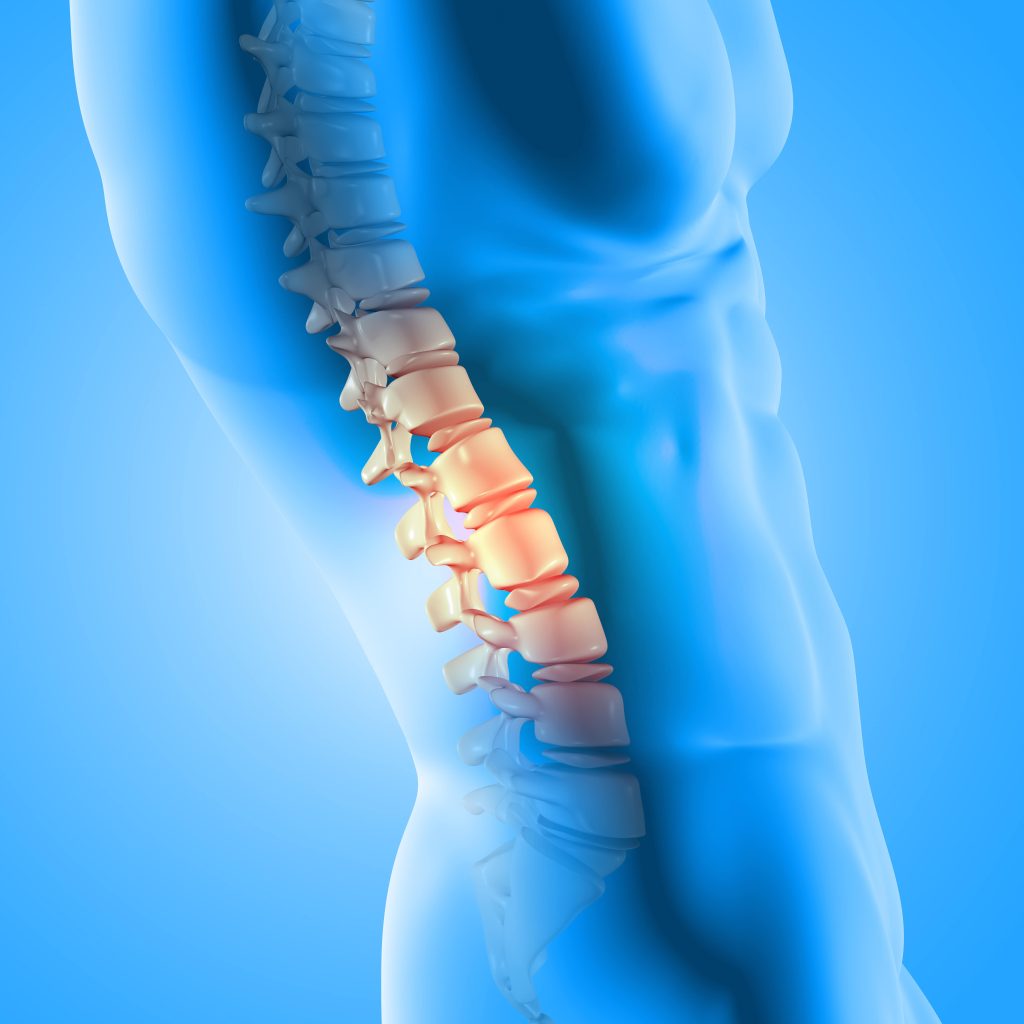

Apa itu Herniated Discs?

Herniated discs, juga dikenali sebagai slipped disc atau prolapsed disc, berlaku apabila cakera lembut antara tulang belakang terkeluar dari kedudukan asal dan menekan saraf berdekatan. Keadaan ini sering berlaku pada bahagian lumbar (pinggang), tetapi juga boleh berlaku di bahagian serviks (leher).

Simptom utama termasuk:

- Sakit belakang yang kronik

- Kebas atau rasa mencucuk pada anggota badan

- Kelemahan otot

- Kesukaran berdiri atau berjalan lama